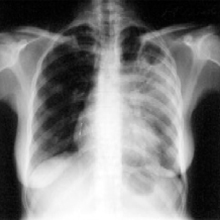

Кількість хворих на туберкульоз зменшилася

У 2008 році в Херсонській області захворюваність на туберкульоз зменшилася на 18,2%, а в окремих районах (Бериславський і Комсомольський в м. Херсон) — у 1,8 рази.

Середньорічний рівень захворюваності на туберкульоз торік — 123,8 випадків захворювання на активний туберкульоз на 100 тисяч жителів області. Для порівняння, у 2007 році у Херсонській області було зареєстровано 151,4 випадки захворювання активний туберкульоз на 100 тисяч населення при загальноукраїнському показнику — 79,8 хворих.

Покращилася лабораторна діагностика бактеріального туберкульозу легень у лабораторіях районних і міських лікарень. Поліпшилася якість лікування хворих на туберкульоз у закладах охорони здоров“я, йдеться в повідомленні. У 2008 році вилікувано 1 тис. 354 особи.